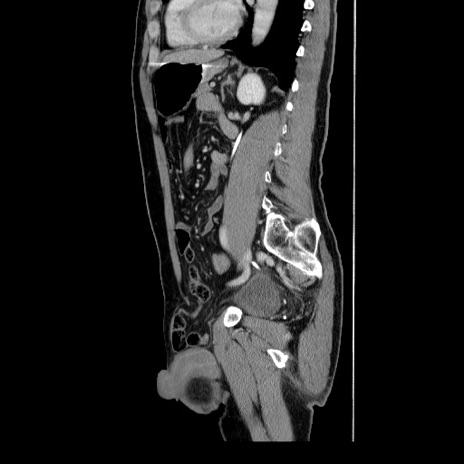

症例34(矢状断像)

【症例】60歳代 男性

【主訴】右鼠径部膨隆

【現病歴】1年程前より右鼠径部膨隆あり。自己にて還納可能だったため放置していた。3時間前より右鼠径部の脱出を認め、還納困難となり受診。

【身体所見】右鼠径部に小児頭大の膨隆あり。弾性硬であり、用手還納は困難。左鼠径部にも膨隆を認める。脱出はなし。